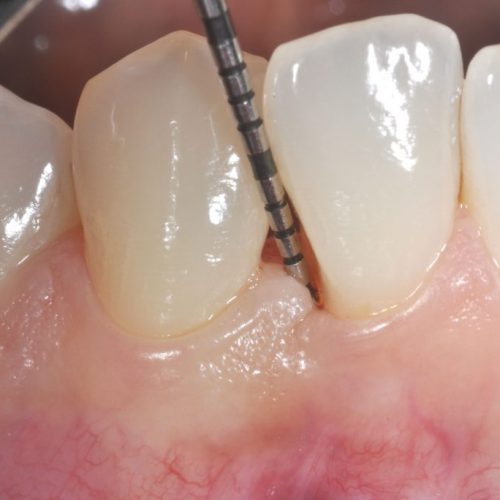

ApprofondisciPARODONTOLOGIA

La Parodontologia è quella branca dell’Odontoiatria che si occupa dello studio e della terapia dei tessuti molli e duri che circondano i denti e che ne assicurano la stabilità e il mantenimento funzionale ed estetico.